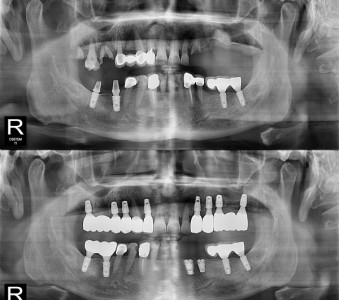

以成果证明实力。

国际摩牙齿科

真实临床案例